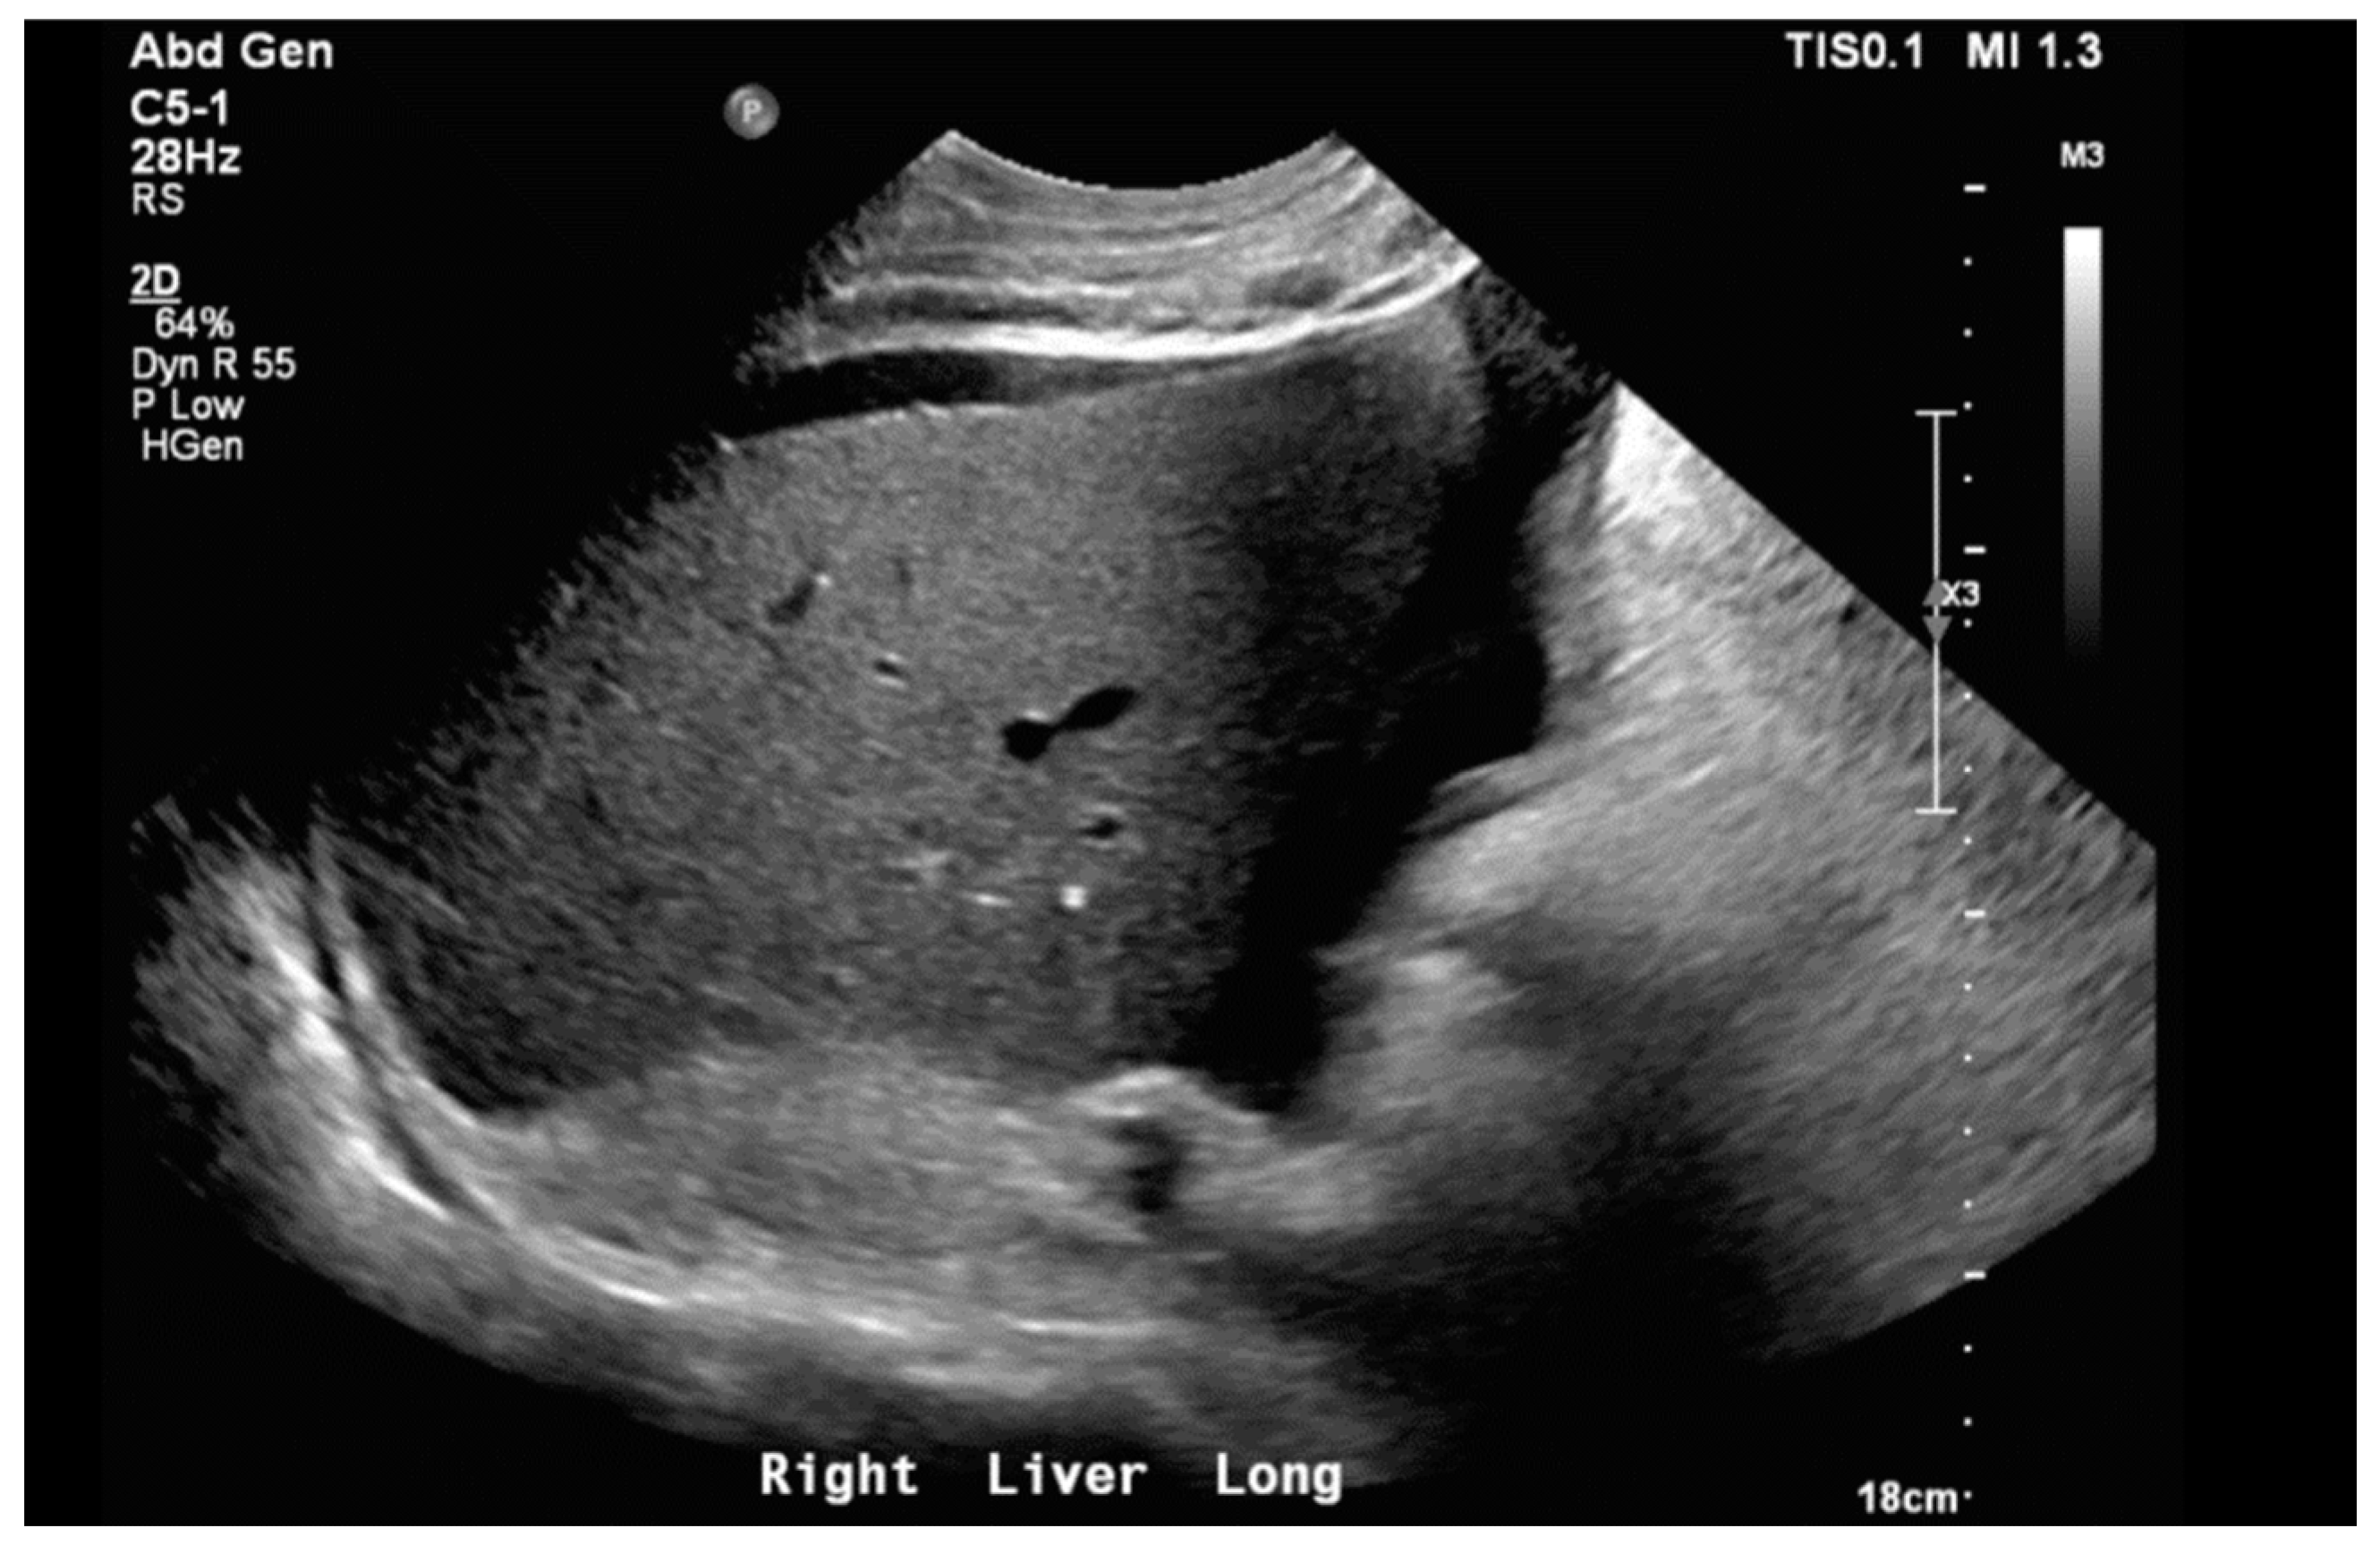

Notable normal admitting lab values included the following: aspartate aminotransferase, alanine transaminase, alkaline phosphatase, bilirubin, platelet count, and international normalized ratio. Creatinine on arrival was 0.79 mg/dL and white blood cell count was 6.0 cells/μL. The only noteworthy abnormal lab was an elevated brain natriuretic peptide of 864 pg/mL. Venous blood gas on arrival with pH of 7.353, pCO2 55.9 mmHg, HCO3 31.1 mmHg, and pO2 21 mmHg. Large-volume paracentesis was performed (5 L), with fluid analysis revealing a serum–ascites albumin gradient (SAAG) of 1.2 g/dL and total protein of 2.6 g/dL. The total nucleated cell count was 1020 cells/mm3 with a polymorphic nucleated cell count (PMN) of 663 cells/mm3, consistent with SBP. The bacterial culture of peritoneal fluid did not grow any organism. An abdominal ultrasound revealed nodular contours within the liver and heterogeneous echotexture compatible with cirrhosis (Figure 1). Doppler imaging of the liver showed patent vessels. Repeat TTE on this admission showed a preserved EF of 65% with paradoxical septal motion, flattened interventricular septum, and severe right ventricular (RV) enlargement consistent with RV pressure/volume overload. The pulmonary systolic pressure was estimated at 74 mmHg (Figure 2). Additionally, the patient was found to have moderate tricuspid regurgitation with a maximum velocity of 385 cm/second (Figure 3).

Following paracentesis, the patient was transfused 50 g of 25% albumin per American Association for the Study of Liver Disease (AASLD) guidelines. Upon results of fluid analysis indicating SBP, he was treated with Ceftriaxone 2 g intravenously daily for seven days, followed by lifelong prophylaxis with oral Ciprofloxacin 500 mg daily. In light of the patient’s signs of volume overload and right heart failure, the decision was made to not follow SBP protocol, which would have called for additional albumin. It is important to note that the guidelines for the management of SBP have been written by the AASLD specifically for SBP in hepatic cirrhosis [8]. There are currently no guidelines on management in ascites from other sources. Although this patient’s abdominal ultrasound showed coarsened echotexture within the liver and ascites, he had no other signs or manifestations consistent with cirrhosis. Given his normal liver synthetic function and Model for End-Stage Liver Disease 3.0 score of 8, these findings on ultrasound were felt to represent structural changes of congestive hepatopathy and not a primary process.

Figure 1. Liver ultrasound in right long axis demonstrating nodular contours with coarsened echotexture. Moderate volume ascites can also be seen.